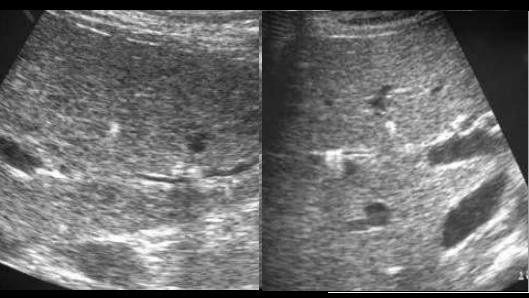

Angiocholite aigue

bacterienne . Image de dilatation

hypoechoriche des voies biliaires

intrahepatiques avec epaissisement legere de

sa paroi ( fleche rouge ) . Image

echographique per cutanee , coupe

hypochondre droit a travers foie droit |

Cholangite infectueuise aigue de

voie biliaire intrahepatique . Image de

dilate tres marque des voie biliaire du foie

droit avec distendue du canal hepatique

commun . Epaississement legere de la

paroi intrahepatique |